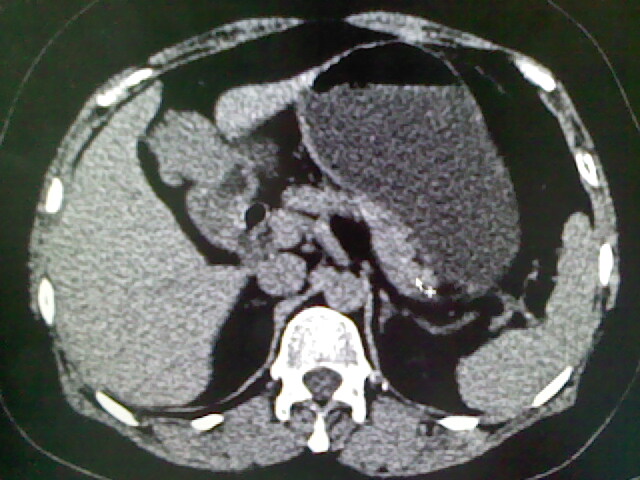

以下是引用卜一在2009-4-2 13:26:00的发言:[br]胆囊颈部结石伴胆囊炎!另:建议增强,待除外肝内占位及胆囊占位!

以下是引用liaoqiang在2009-4-2 16:23:00的发言:[br]胆囊是否切除?胆囊颈区致密影考虑金属夹?结石?肝脏右叶低密度影,考虑增强。